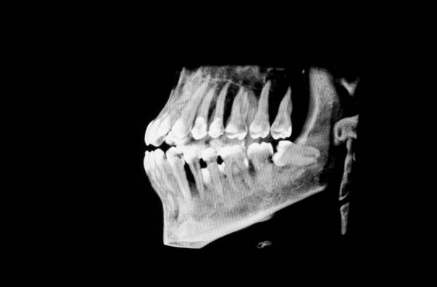

Before your dental surgery in Lakeland, you will meet with your dentist or oral surgeon to go over the procedure. During regular checkups, your dentist will examine your wisdom teeth and take X-rays to see their position. This allows your dentist to determine whether the teeth are affected or can be safely removed.